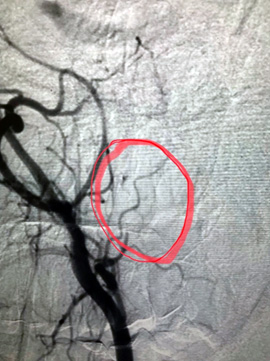

Было принято решение о проведении хирургического вмешательства. С учетом генеза образования первый этап вмешательства выполнили эндоваскулярные хирурги. Ангиография подтвердила сосудистый характер опухоли, помогла определить размеры, распространенность и источники кровоснабжения и определить объем предстоящей операции. Произведена эмболизация образования среднего уха справа с положительным эффектом.

— Через правую лучевую артерию была выполнена катетеризация правой наружной сонной артерии. С помощью ангиографии была выявлена ветвь наружной сонной артерии, питающая опухоль. Микрокатетер был заведен в эту ветвь и подведен непосредственно к опухоли. С помощью эмболизационных частиц размером 700 нм выполнена селективная эмболизация опухоли, что привело к полному прекращению ее кровоснабжения. Катетер был удален, на место пункции наложена повязка. Доступ через лучевую артерию является одним из самых безопасных и не требует строгого соблюдения постельного режима после процедуры, что, несомненно, делает пребывание в стационаре намного комфортнее.